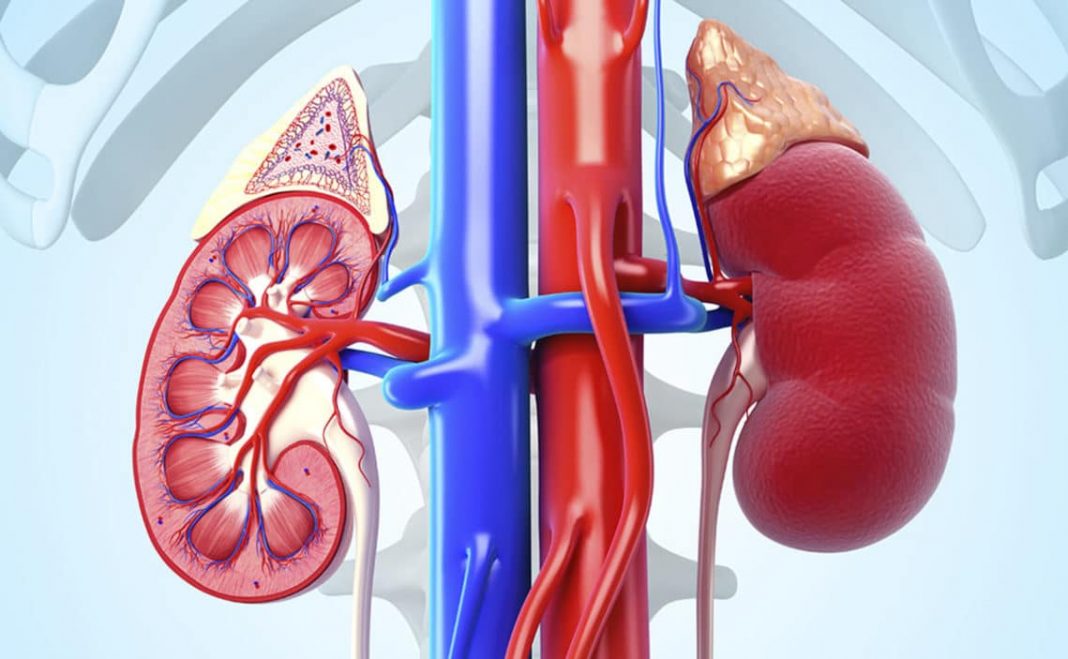

7También podría afectar a los riñones

De acuerdo a los expertos, otro de los posibles efectos adversos más comunes cuando tomamos ibuprofeno es que este medicamento puede terminar afectando a algunos de nuestros órganos vitales.

Entre ellos, destaca su acción en los riñones. Este antiinflamatorio no esteroideo puede producir lesiones crónicas en los mismos así como la eliminación de algunas de las sustancias participantes en el dolor.